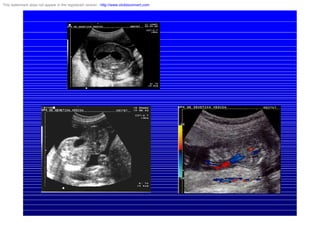

Cardíacas

• 0,8 % de recién nacidos

• Diagnóstico prenatal: 25 % anomalías

cromosómicas

• 2 % agentes ambientales

• 2-3 % de recurrencia y con dos hijos afectados:

10 %

– Defectos septo auriculo-ventriculares

• CANAL A-V: 50 % anomalía de cromosomas:

60 % T21 y 25 % T 18

• Diagnóstico relativamente fácil

• pronóstico pobre por anomalías asociadas

– Malformaciones conotruncales : deleción 22

This watermark does not appear in the registered version - http://www.clicktoconvert.com

Indicaciones de ecocardiograma fetal